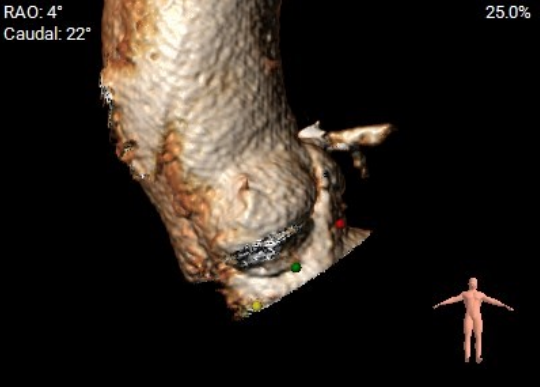

血管三维重建

术前主动脉CTA评估:主动脉瓣三叶式,瓣叶基本等大,瓣叶稍增厚,左右瓣叶游离缘轻微钙化;主动脉瓣环周长折算直径约27.6mm;双侧冠脉开口高度可LCA:13.7mm,RCA:17.3mm;左侧冠脉轻度钙化;术中建议造影角度RAO:4°,CAU:22°;降主动脉及双侧髂总动脉轻微钙化,走行迂曲;双侧髂总动脉稍增宽;双侧髂外动脉迂曲。

右窦居中位:LAO:4° CAU:22°

主动脉瓣环夹角:44°